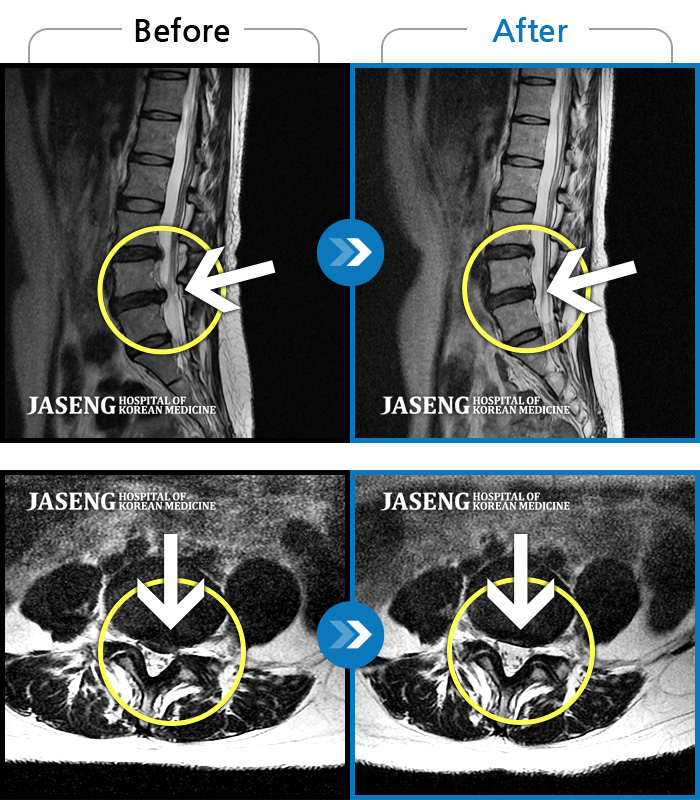

Before

After

환자에게 사전 동의를 받아 동일 조건에서 촬영되었습니다.

개인에 따라 치료 후 부작용이 발생할 수 있으니 의료진과 상담 후 치료를 진행하시기 바랍니다.

좌측 다리 저림 증상이 너무 심하여 야간에 주무시기도 어려운 상태

통증 때문에 휴직 후 여러 치료에도 호전이 없던 다리 통증 및 저림